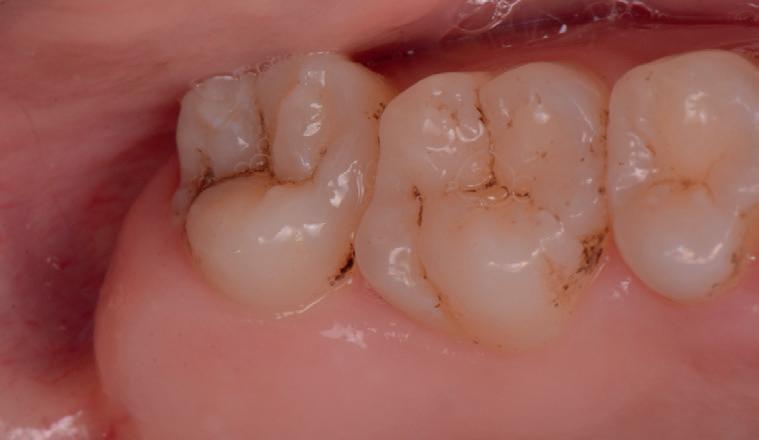

RECONSTITUIREA țesuturilor moi periimplantare. Scopul acestui raport de caz este de a demonstra procedurile chirurgicale utilizate pentru corectarea unui defect al țesuturilor moi periimplantare folosind țesutul moale interdentar în combinație cu tuberozitatea ca locație donatoare de țesut conjunctiv, utilizând o abordare prin tunelizare într-o zonă estetică.